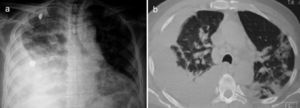

A 67-year-old male subject was hospitalised due to one-week course dyspnoea and fever. Upon admission, the patient was in poor general condition and with a SatO2 of 78% at room temperature. His vital signs were the following: RR 29min, HR 112min, BP 145/85mmHg and a temperature of 37°C. Physical examination showed a right-sided pleural effusion syndrome and very scarce fine crackles in the left hemithorax. The chest X-ray and computed tomography showed bilateral alveolar opacities and verified the presence of a right-sided pleural effusion (Fig. 1). Laboratory results only showed leukocytosis of 21,400cells/μL, out of which 9400cells/μL corresponded to lymphocytes. The patient showed no increased nitrogen compounds, and the general urinalysis showed no signs of sediment or proteinuria. In thoracentesis, a thick yellow fluid was obtained with a pH 7.0; protein 6g/dL; glucose 22mg/dL; LDH 1.066U/L, scarce polymorphonuclear cells without the presence of Gram staining bacteria. The patient was initially treated for pneumonia associated with a complicated pleural effusion and was intubated through the right hemithorax and started receiving IV moxifloxacin 400mg every 24h and IV meropenem 1g every 8h; subsequently, said schedule was replaced by IV vancomycin 500mg every 6h and IV piperacillin 4g/tazobactam 0.5g every 6h. However, during the following days no clinical or radiological improvement was observed, and pleural fluid drainage persisted despite said antimicrobial schedules. The results of the acid-fast bacilli smear, pleural fluid cultures, and blood cultures were negative. After a lengthy hospital stay, the patient showed systemic dermatosis (Fig. 2a), and in a skin biopsy, a lymphocytic vasculitis (Fig. 2c) was documented. This scenario was initially attributed to an antimicrobial adverse effect. Viral hepatitis B and C, HIV, VDRL, pANCA and cANCA profiles were all negative. It was only after a detailed physical exam that some ulcers were found in the penis (Fig. 2b); however, the result of the pathergy test was not conclusive. The case was diagnosed as an incomplete form of Behçet's disease versus ANCA-negative Wegener's granulomatosis; for this reason, the patient was treated with IV methylprednisolone 125mg every 6h, showing a rapid improvement in his general and breathing conditions, which enabled the successful removal of thoracic intubation and hospital discharge soon after having started treatment. Unluckily, the patient died a few weeks later due to a clinical picture of diffuse alveolar haemorrhage.